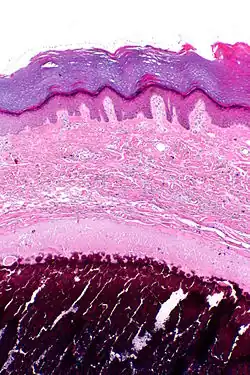

| Micrograph of calcinosis cutis. The calcification is purple (bottom of image). H&E stain. | |

Histopathology of calcinosis cutis in human tissue